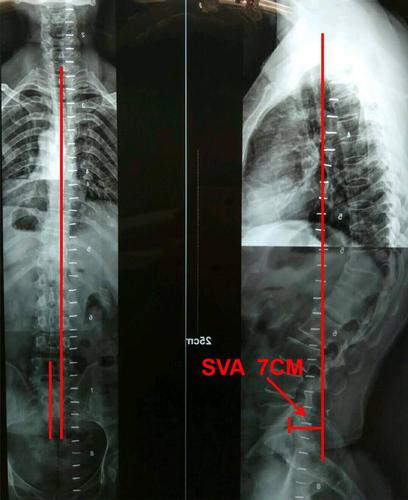

先天性脊柱后凸

先天性脊柱后凸,先天性脊柱侧凸

先天性脊柱后凸畸形图

先天性脊柱后凸图片

脊柱后凸畸形图片

脊柱后凸

脊柱后凸图片

胸椎后凸